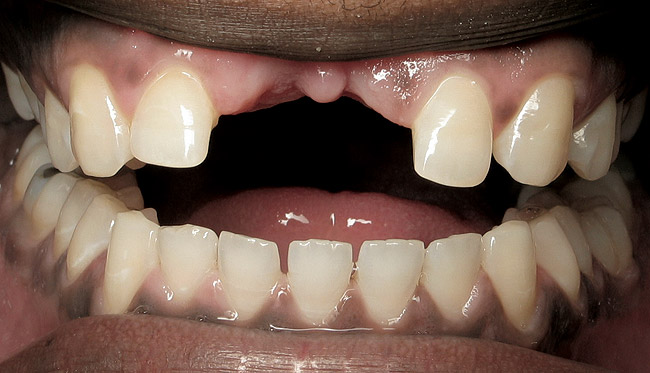

Figure 17  ENDODONTIC AND ESTHETIC PARAMETERS  The loss of teeth Nos. 8 and 9 led to a soft-tissue defect that will result in asymmetric papilla heights > 1 mm. This may be esthetically unacceptable to the patient.

Figure 17

Figure 18  ENDODONTIC AND ESTHETIC PARAMETERS  The restoration in place shows asymmetry in the papilla of teeth Nos. 8 through 10. Soft-tissue changes should always be considered when extraction is proposed.

Figure 18